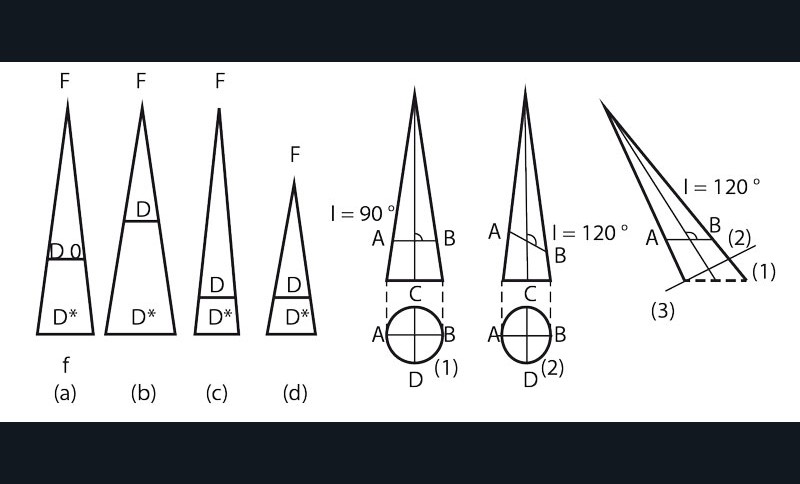

• L’image conventionnelle ne peut donc prétendre à l’exactitude anatomique. De plus, elle varie :

– dans ses dimensions selon la distance foyer Rx-récepteur, foyer-dent, dent-récepteur ;

– pour sa forme suivant l’orthogonalité ou l’obliquité du rayonnement par rapport au récepteur (fig. 1).